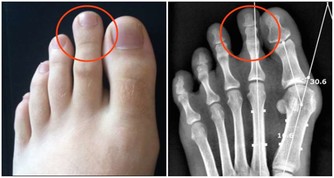

測試五:看嘴唇顏色

看肺部是否健康,就看下嘴唇是不是發紫,肺功能不好的人因為缺氧會有一定程度的紫紺。如果嘴唇紅潤,說明肺部沒有病變發生。